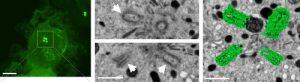

Neu entdeckter Prozess bringt Immunzellen auf Trab17. Oktober 2022 Dendritische Zelle, in der sich nach Kontakt zu einem Antigen zwei Zentrosomen mit vier sogenannten Zentriolen (grüne Punkte) gebildet haben. Bild: © Miroslav Hons / Karls-Universität Vestec Krebszellen nutzen einen ungewöhnlichen Mechanismus, um in neues Gewebe einzuwandern und dort Metastasen zu bilden. Derselbe Prozess bringt wohl auch manche Immunzellen auf Trab. Das belegt eine aktuelle Studie unter Federführung der Universität Bonn. In den Zellen vermehren sich demnach bestimmte Strukturen, die Zentriolen. Dadurch können sie besser ihre Richtung halten und so rascher in die Lymphknoten wandern, wo sie andere Abwehrzellen aktivieren. Die Ergebnisse sind nun im “Journal of Cell Biology” erschienen. Das Immunsystem setzt wie die Polizei auf Arbeitsteilung. Da sind zunächst einmal die dendritischen Zellen. Sie suchen rund um die Uhr im Gewebe nach Spuren verdächtiger Eindringlinge, Antigene genannt. Bei Erfolg eilen sie zu den Lymphgefäßen und darüber in die Lymphknoten. Dort präsentieren sie ihre Funde einem schlagkräftigen Fahndungsteam, den T-Zellen. Diese körpereigenen Truppen wissen nun, gegen welchen Feind sie vorgehen sollen.Diese Attacke muss erfolgen, bevor die Eindringlinge größeren Schaden anrichten oder sich zu sehr vermehren. Daher ist es wichtig, dass die dendritischen Zellen möglichst rasch zu dem Briefing im Lymphknoten wandern. „Wir haben einen Mechanismus entdeckt, der ihnen dabei hilft“, erklärt Prof. Eva Kiermaier vom LIMES-Institut (Life and Medical Sciences) der Universität Bonn. „Sie bilden dazu vermehrt bestimmte Strukturen, Zentrosomen genannt. Diese helfen ihnen, länger ihre Richtung zu halten und so schneller zu den Lymphgefäßen zu gelangen.“Wichtige Funktion bei der ZellteilungZentrosomen zählen zu den Organellen – das sind Molekülkomplexe, die in Zellen für bestimmte Aufgaben zuständig sind, ganz ähnlich wie die Organe im Körper. Normalerweise gibt es in jeder menschlichen Zelle genau ein Zentrosom. Kurz vor der Zellteilung verdoppelt es sich. Die beiden Kopien wandern in entgegengesetzte Pole der Zelle und spannen zwischen sich ein Bündel von Fasern auf, die Mikrotubuli. Mit ihnen ziehen sie bei der Teilung die Chromosomen (die sich ebenfalls verdoppelt haben) auseinander. Jede der entstehenden Tochterzellen erhält so einen kompletten Satz von Erbanlagen sowie eines der beiden Zentrosomen. Das Bild zeigt eine dendritische Zelle, in der sich nach Kontakt zu einem Antigen zwei Zentrosomen mit vier sogenannten Zentriolen (grüne Punkte links; rechts daneben weiter vergrößert) gebildet haben. Bild: © Miroslav Hons / Karls-Universität Vestec „Zentrosomen sind aber auch dafür zuständig, das Zytoskelett während der Zellwanderung zu organisieren“, betont Kiermaier, die 2017 durch das Rückkehrerinnen-Programm des Landes Nordrhein-Westfalen von Niederösterreich (IST Austria, Klosterneuburg) an den Rhein geholt wurde. „Darunter verstehen wir faserartige Struktur-Proteine, die der Zelle ihre Form geben und ihr Stabilität verleihen.“ Das Zytoskelett entscheidet auch darüber, wo bei einer Zelle „vorne“ und „hinten“ ist. Und das hat wiederum Einfluss auf ihre Bewegungsrichtung. „Wir konnten nun zeigen, dass dendritische Zellen mehrere Zentrosomen bilden, sobald sie mit einem Antigen in Kontakt gekommen sind“, sagt Ann-Kathrin Weier. Die Doktorandin am LIMES-Institut teilt sich mit ihrer Kollegin Mirka Homrich die Erstautorenschaft der Publikation. Beide haben wichtige Teile der Experimente durchgeführt. Länger Kurs halten, um flotter ans Ziel zu kommenDendritische Zellen haben nämlich ein Problem: Sie wissen nicht, wo das nächste Lymphgefäß ist, über das sie in den Lymphknoten gelangen können. Bei ihrer Suche verfahren sie nach der Strategie „Versuch und Irrtum“: Sie laufen eine kurze Weile in eine Richtung und wechseln diese dann, wenn sie dabei auf kein Gefäß gestoßen sind. „Je mehr Zentrosomen sie haben, desto länger halten sie Kurs, bevor sie in einer anderen Richtung weitersuchen“, sagt Homrich. „Wir konnten in Computersimulationen zeigen, dass sie dadurch die Lymphgefäße deutlich schneller finden als normalerweise.“ Dabei wird durch die Vermehrung der Zentrosomen ihr Durchhaltevermögen genau passend justiert – sie halten also nicht zu störrisch an ihrer Richtung fest. Denn dann würde die Gefahr steigen, dass sie auf Abwege geraten und sich komplett „verrennen“.Der in der Studie identifizierte Mechanismus war bei gesunden Zellen bislang völlig unbekannt. Von Krebszellen wusste man, dass sie ihn nutzen, um Metastasen zu bilden. Dazu dürfen die vervielfachten Zentrosomen aber nicht frei verteilt in ihrem Innern liegen. Denn sonst würden sie Funktionen wie die Zellteilung empfindlich stören. Sowohl in Tumor- als auch in den dendritischen Zellen versammeln sich die Organellen daher an einer einzigen Stelle – sie kondensieren. „Es gibt inzwischen Wirkstoffe, die diese Kondensation der Zentrosomen stören“, sagt Kiermaier, die auch Mitglied im Exzellenzcluster ImmunoSensation2 und im Transdisziplinären Forschungsbereich „Leben und Gesundheit“ der Universität Bonn ist. „Dadurch können sich die Krebszellen nicht mehr korrekt teilen, sondern sterben ab.“Möglicherweise stören diese Substanzen aber auch das Immunsystem – schließlich kondensieren die Zentrosomen auch dort. „Wir haben verschiedene dieser Wirkstoffe in Zellkulturen getestet“, sagt sie. „Dabei haben wir tatsächlich Anzeichen dafür gefunden, dass sie die Schlagkraft der Immunabwehr erheblich beeinträchtigen könnten.“ Würde sich das in klinischen Studien bestätigen, wäre das eine schlechte Nachricht. Denn dann müsste man bei Einsatz der Wirkstoffe in der Krebstherapie erhebliche Nebenwirkungen befürchten.Beteiligte Institutionen und Förderung: An den Arbeiten waren neben der Universität Bonn die Karls-Universität in Vestec, Tschechien, sowie die Institute für Wissenschaft und Technologie in Österreich und Spanien beteiligt. Die Studie wurde durch die Deutsche Forschungsgemeinschaft (DFG), das Ministerium für Innovation, Wissenschaft und Forschung NRW, die Chan- Zuckerberg-Initiative (USA) sowie die tschechische Forschungsstiftung gefördert.